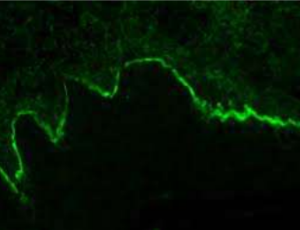

Direct immunofluorescence pattern:

Autoantibodies (usually IgG or IgM) and complement component (usually C3) can be demonstrated in the intercellular spaces between the epithelial cells in almost all patients with this disease( "chicken wire' pattern)

Direct Immunofluorescence Pemphigus Vulgaris, Pemphigus, or Lichen Planus (Michel's solution)

Direct Immunofluorescence specimen in MICHEL'S

solution

Autoantibodies are seen to bind around the edges of prickle cells at site of desmosomes